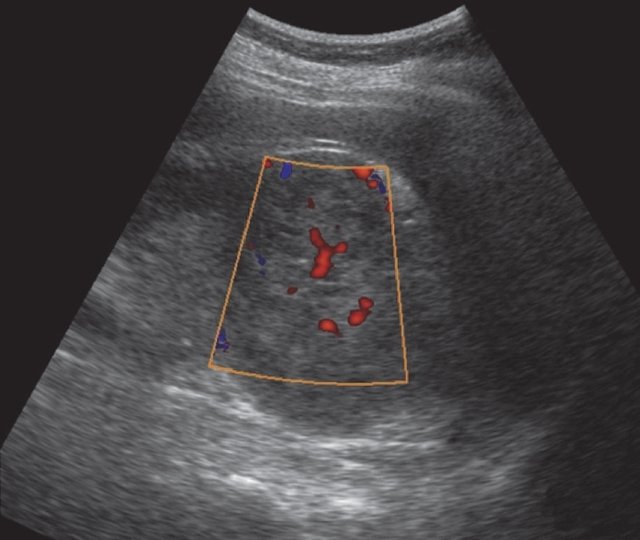

ЦДК сосудов почек: что это и как проводится

Раздел: Фотоэссе